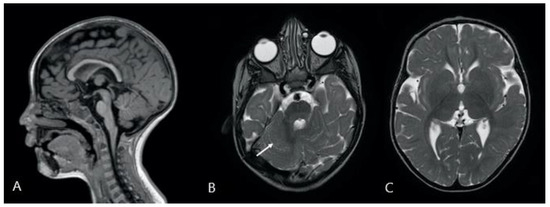

| 20 | p15, q26.1 | + | + | + | + | Stereotypies | Temporo-parietal BL rapid rhythms, posterior slowing | None | MRI: posterior cranial fossa and CC abnormalities | Present case |